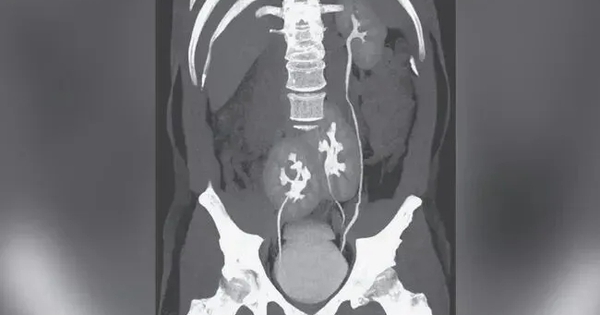

Đi khám nhiễm trùng tiết niệu, người đàn ông 31 tuổi phát hiện có 3 quả thận

Bệnh nhân thậm chí không bao giờ nhận ra mình có thêm một quả thận trong suốt cuộc đời.